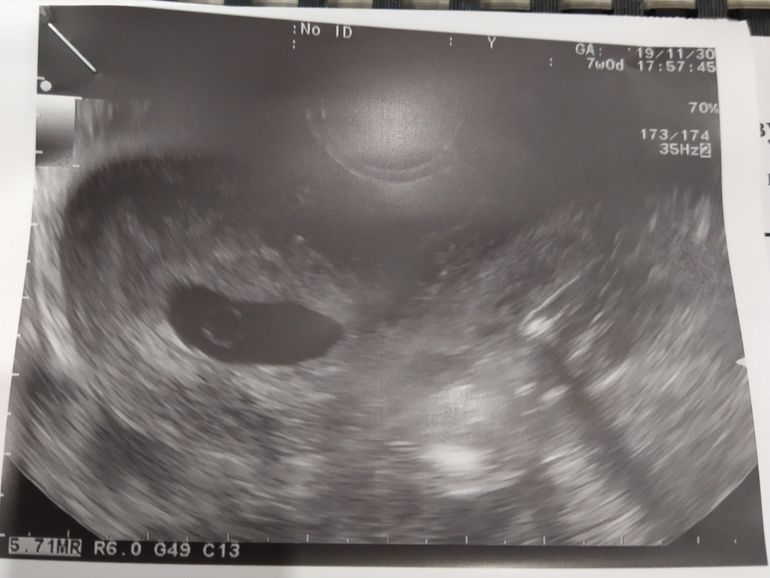

УЗИДевочки, у меня вопрос, по узи срок 7+4, пя 25, но похоже пустое. По месячеым 6+4. Я пошла к врачу, только из-за кровртечения , оказывается у меня скорее всего 2пч было и одно вышло. Второе пока в норме.Все признаки беременности на месте, тошнота, грудь стала немного больше, слабость.

Вот на фото ваш желточный мешочек

А вот моя анэмбриония с желточным мешочком